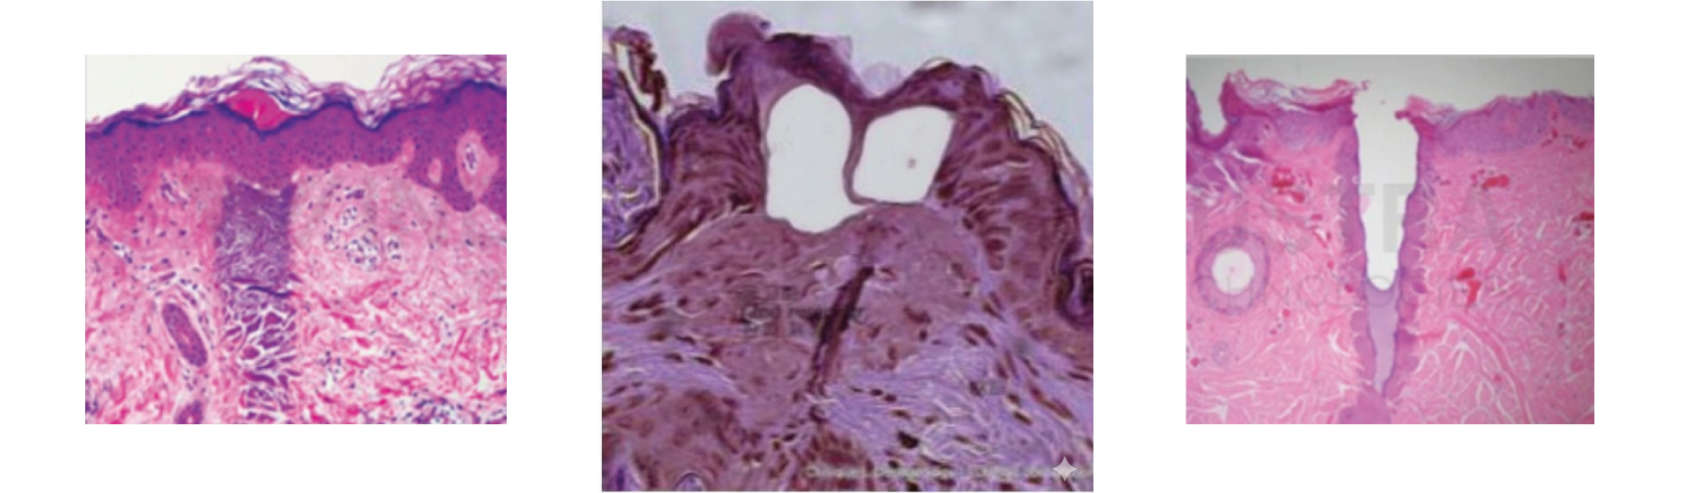

Cómo actúa el láser Tulio 1927 en la piel

Estimulación de colágeno y elastina: El depósito térmico focalizado desencadena respuesta reparativa con neocolagénesis y neoelastogénesis, mejorando firmeza y luminosidad progresivamente en las semanas posteriores.

Microcanales para drug delivery: Las microcolumnas dejan microcanales transitorios que facilitan la penetración de activos tópicos seleccionados, optimizando protocolos combinados en discromías y retexturización.

El Láser Tulio 1927 es un láser fraccional de fibra diseñado para trabajar ablativo o subablativo según energía, con alta absorción en agua para actuar de forma precisa en epidermis y dermis superficial. Incorpora cabezal estático (matrices 3×3 a 20×20 mm) y dinámico con rodillos y detección magnética, lo que permite entregar cobertura homogénea en barridos rápidos y controlados.